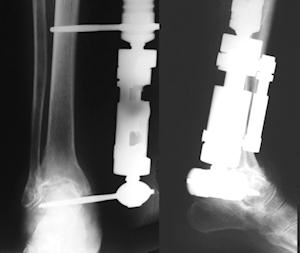

Van Roermund tarafından önce ayak bileği ekleminde tariflenen ve daha sonra diğer eklemlerde de uygulanan bu teknikte, ayak bileği sirküler eksternal fiksatör içinde distrakte edilerek 3 ay süreyle tutulur. Bu süre zarfında fiksatör içinde yüklenmeye izin verilir. Bu yöntemle, klinik düzelmenin yanında radyolojik eklem mesafesinde artış ve subkondral sklerozda azalma olduğu bildirilmiştir. 22 olgunun 7 yıllık izleminde yöntemi tarif eden yazarlar %73 başarılı sonuç rapor etmişlerdir (Ploegmakers JJ: Osteoarthritis Cartilage. 2005, 13:582-8.) Buna karşın hayvan deneylerinde, kıkırdak histolojisi ve proteoglikan içeriğinde bir değişme olmadığı saptanması, yöntemin etki mekanizması hakkında hala bilinmeyen yönlerin olduğunu düşündürmektedir (van Valburg AA, Osteoarthritis Cartilage. 2000, 8:1-8. )Düzeltici osteotomi